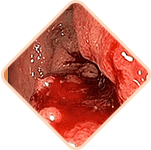

Idegen test érzése, nehézségérzés a végbélben.

Viszketés és égő érzés a végbélnyílásnál.

Fájdalom ürítéskor, járáskor és ülő helyzetben.

Az aranyeres csomók fájdalma tapintásra

Vérzés ürítés közben vagy megerőltetés esetén